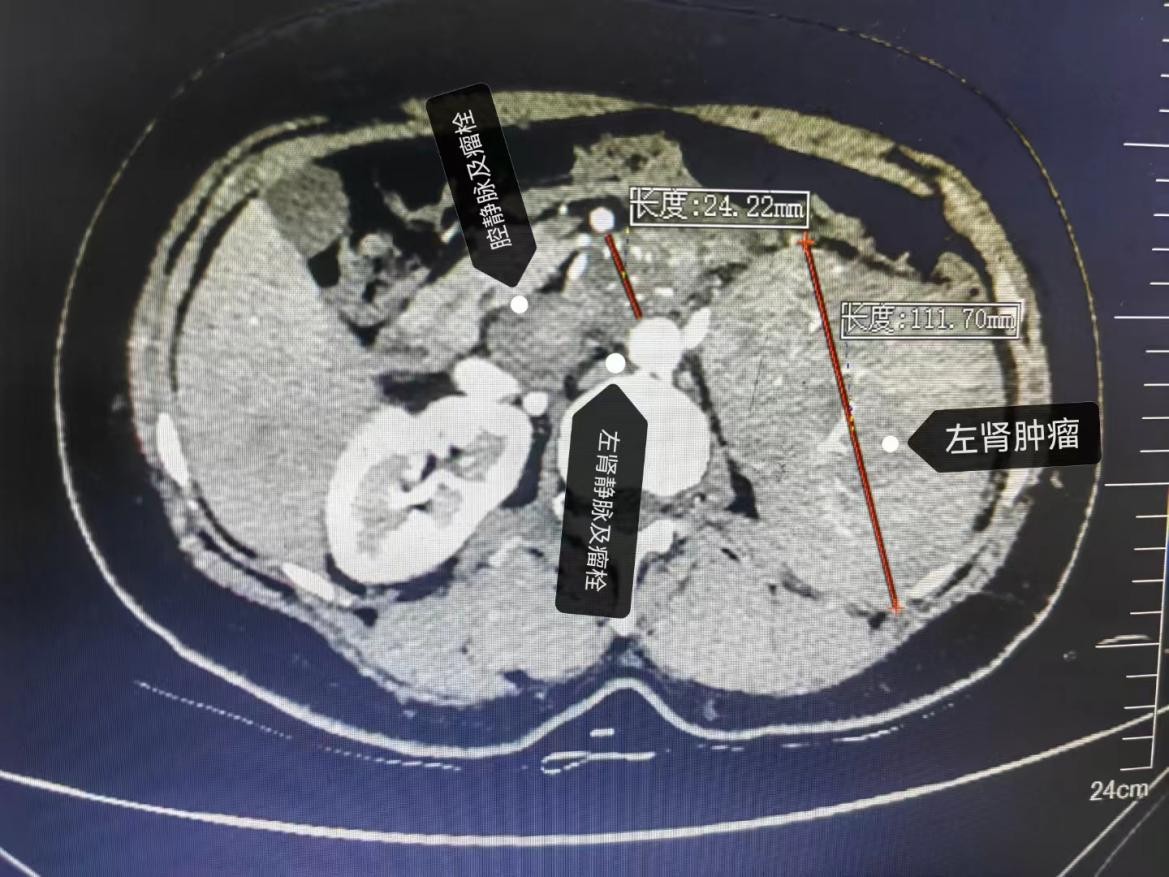

近日,45岁的黄女士日前因“间歇性性尿血伴腰痛3天”就诊于自治区南溪山医院。经检查结果发现一个直径超10cm的巨大左侧肾肿瘤且伴肾静脉瘤栓及下腔静脉瘤栓!目前肾癌伴肾静脉癌栓及下腔静脉癌栓最有效的治疗方法是行肾根治性切除术+肾静脉瘤栓取栓术+下腔静脉瘤栓取栓术,但手术中极易出现瘤栓脱落而导致猝死,手术风险极高,术中需精准分离下腔静脉、肾静脉等大血管,且该患者癌栓直径近3厘米,肿瘤巨大,导致空间狭小、分离困难。该手术是泌尿外科超高难度的标志性手术,也被称之为“皇冠上的明珠”。

泌尿外科主任廖松柏博士团队为其进行充分的术前检查及围手术期评估。为保证患者安全,为了给患者提供最佳的治疗方案,泌尿外科联合心脏大血管外科、手术麻醉科、重症医学科等多个学科的专家进行多学科联合会诊,结合患者病史、症状体征、影像学资料及国内外的治疗经验,对患者进行了全面评估,将术中可能遇到的情况及处理预案进行逐一推演,共同制定了围手术期的治疗与护理方案。考虑到患者做左肾肿瘤大,左侧肾静脉癌栓长,已充满整个肾静脉,并进入下腔静脉,而且癌栓直径粗,术中会粘连,手术难度大,出血多,为了减少术中出血量等问题,经泌尿外科团队联合多学科多次讨论,廖松柏主任亲切的与患者交流,缓解患者紧张的情绪,最终决定拟行在全麻下行左侧肾根治性切除术+左肾静脉瘤栓取栓术+下腔静脉瘤栓取栓术+下腔静脉缝合术。